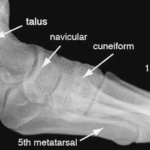

Las radiografías, generalmente llamadas rayos X, producen imágenes como sombras de huesos y ciertos órganos y tejidos. Las radiografías son muy buenas para detectar problemas óseos. Pueden mostrar algunos órganos y tejidos blandos; sin embargo, la MRI y la CT suelen crear mejores imágenes de los mismos. Aun así, las radiografías son rápidas, fáciles de obtener y menos costosas que los otros estudios, por lo que se pueden usar para obtener información rápidamente.

Un tubo especial dentro de la máquina de rayos X emite un haz de radiación controlada. Los tejidos del cuerpo absorben o bloquean la radiación en diferentes grados. Los tejidos densos como los huesos bloquean la mayor parte de la radiación, pero los tejidos blandos, como la grasa o los músculos, bloquean menos radiación. Después de pasar por el cuerpo, el haz alcanza una pieza de un fragmento de película o un detector especial. Los tejidos que bloquean altas cantidades de radiación, como los huesos, aparecen como áreas blancas en un fondo negro. Los tejidos blandos bloquean menos radiación y aparecen en tonos de gris. Los órganos que contienen principalmente aire (como los pulmones) aparecen en negro. Los tumores son por lo general más densos que el tejido que los rodea, por lo que suelen verse en tonos grises más claros.